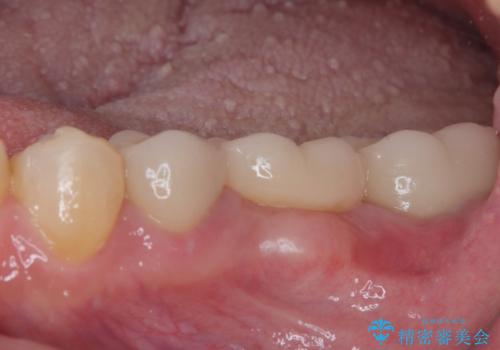

まずは奥歯の痛みを改善し、その後矯正治療を行い、最後にオールセラミックブリッジによる補綴治療を行うこととしました。

むし歯をきっかけに矯正治療を行うこととなりましたが、学生の頃から気になっていた歯列を改善することができ、患者様には大変満足していただけました。